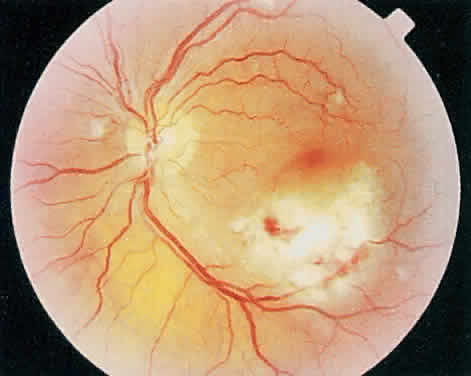

mild anterior uveitis is extremely unusual with AIDS-associated CMV retinitis. The hallmark lesion of CMV retinitis is a necrotizing, full-thickness retinitis that results in retinal cell destruction. CMV often initially affects retinal tissue adjacent to major retinal blood vessels or the optic disc (Fig. 1). This is consistent with the concept that the virus is spread to the retina hematogenously. In most cases, the pattern of infection is classic and distinctive, making clinical diagnosis straightforward. The area of active retinitis has a granular, dirty-white appearance. As the virus attacks the endothelial cells of blood vessels, hemorrhage is common. Advancement in the retinitis by both direct cell-to-cell transmission as well as spread by way of adjacent satellite lesions can be seen. Except for cases in which retinitis is acute, it is common to see areas of healed retinitis beside areas of active necrosis. Areas of burned-out necrosis show absence of any retinal tissue, whereas the underlying retinal pigment epithelium assumes a “salt and pepper” appearance. CMV retinitis can present initially as either large areas of retinal necrosis with hemorrhage or one or more small, focal areas of retinal whitening.1,12,14 These small, focal lesions may on occasion be confused with cotton-wool spots or lesions of toxoplasmosis.5,27 Unlike cotton-wool spots, focal areas of CMV may appear outside the posterior pole. These early, focal infiltrates of CMV may not be associated with retinal hemorrhages or vitreous cells. Over a course that usually spans weeks, infiltrates of CMV tend to assume two different patterns of clinical disease.11,12 The first pattern is called hemorrhagic and is characterized by broad geographic zones of retinal whitening. These large, geographic lesions are usually in close proximity to a major retinal blood vessel or the optic nerve. Satellite lesions are common. When the retinal necrosis associated with CMV retinitis becomes widespread, it is almost invariably associated with retinal hemorrhages. Although the border between necrotic and unaffected retina is sharply demarcated, the border itself appears irregular and jagged. Exudation into the retina or subretinal space may be seen, adding to the granular appearance of the retinitis. Juxtaposition of large zones of white, granular necrosis with those of red retinal hemorrhage has led this appearance of CMV retinitis to be described as either “pizza-pie” or “cheese and ketchup.” The retinal blood vessels, both arteries and veins, in the areas of necrosis commonly appear sheathed, secondary to a vasculitis. As a consequence, secondary retinal vascular occlusions, especially branch retinal vein obstructions, may occur in the course of CMV retinitis. Immune-mediated vascular damage may play a role in the vasculitis.12 Central healing of these lesions will occur as the infection progresses. Avasculitis resembling “frosted branch angiitis” hasbeen reported (Fig. 2).28 A second pattern of CMVretinitis has been labeled “granular” or “brushfireborder.” In this appearance, the focal granular infiltrates enlarge slowly across a line, leaving ever-increasing areas of destroyed retina and atrophic retinal pigment epithelium behind. Hemorrhages and vitreous cells are a less prominent feature. There appears to be direct cell-to-cell transfer of infected virions in this pattern of infection (Figs. 3 and 4). The brushfire border is commonly seen in CMV retinitis lesions anterior to the equator (Fig. 5). The significance, if any, of these two clinical patterns of CMV retinitis is not known, and, in some eyes, both patterns of disease can be seen simultaneously or in sequence. Progression of retinitis has been defined in clinical trials as movement of a lesion border at least 750 μm along a front that is 750 μm or more in length, development of a new CMV lesion in a previously involved eye or in the uninvolved fellow eye of a patient with baseline unilateral disease.29 Without treatment or improvement in the host's immune system, CMV retinitis is a relentless, slowly progressive infection resulting in blindness caused by total retinal necrosis, retinal detachment, or optic nerve involvement, in any combination.

CMV infection can affect the optic nerve either directly or by extension from adjacent retinitis (see Fig. 2).30–32 When direct involvement occurs, optic neuritis with profound, irreversible visual loss usually develops. Several cases of CMV optic neuritis associated with adjacent retinitis have been treated successfully. Exudative retinal detachment can occur during the course of CMV retinitis as well.4,12,30 The subretinal fluid is seen primarily inferiorly in the fundus and shifts with position. No retinal break will be evident; however, in areas of extremely thin, atrophic retina, it can be quite difficult to determine whether a full-thickness defect is present. Exudative retinal detachment associated with CMV is usually nonprogressive and may respond to ganciclovir therapy. Other features may include a mild to moderate anterior chamber cell and flare reaction. A hypopyon has rarely been reported in a renal transplant patient.4 Although mild vitreous cells are almost universally present, a florid vitritis severe enough to result in media opacity rarely develops from isolated CMV retinitis. In one patient who was immunosuppressed as a result of systemic corticosteroid therapy, a severe panuveitis associated with CMV retinitis was reported.32 More recently, an entity called immune recovery retinitis has been described.26,27 Immune-recovery uveitis is a chronic inflammatory syndrome associated with clinical immune reconstitution in AIDS patients with CMV retinitis who are taking HAART.33–35 It has emerged as an important cause of visual morbidity. Although immune recovery associated with HAART has allowed some patients to discontinue specific anti-CMV therapy, the rejuvenated immune response can be associated with this sight-threatening inflammation in some patients with preexisting CMV retinitis. Ocular features of immune-recovery uveitis include a significant vitritis that is more pronounced than that occurring with primary CMV retinitis. Additional features may include optic disc and macular edema. The mean CD4+ T-lymphocyte count in one study was 393 cells/mm3 at the time of diagnosis.33 Long-term vision-threatening complications related to this persistent inflammation include proliferative vitreoretinopathy, epiretinal membrane formation, posterior subcapsular cataracts, and severe postoperative inflammation.36 Rhegmatogenous retinal detachment occurs in 10% to 20% of eyes with CMV retinitis.37–39 However, before the AIDS epidemic, there were only five reported cases of this association.10,40 In patients living more than 1 year with CMV retinitis, risk of retinal detachment may be as high as 50%,41 which increases if more than 25% of peripheral retina is involved by disease.41,42 Retinal breaks in eyes with CMV retinitis typically occur within or at the border of necrotic atrophic retina (Fig. 6).43 The ensuing retinal detachments are typically difficult to repair with standard scleral buckling procedures. This is because of the location and number of retinal breaks, the difficulty in visualizing all breaks in necrotic retina, and the high incidence of associated proliferative vitreoretinopathy. In many cases, pars plana vitrectomy and retinal tamponade with silicone oil or long-acting intraocular gas is indicated (Figs. 7 and 8).37,44,45 However, scleral buckling may be considered in small peripheral retinal detachments when the entire involved area can be completely placed on the element. Laser photocoagulation demarcation has also been described to delimit macula-sparing CMV-related retinal detachment.46 Although anatomic success of macular reattachment with surgery is high, the visual results are often limited by the underlying disease process.47 When considering surgical repair of CMV-induced retinal detachment, consideration should be given to the potential for ambulatory vision, the patient's systemic condition and the status of the fellow eye.